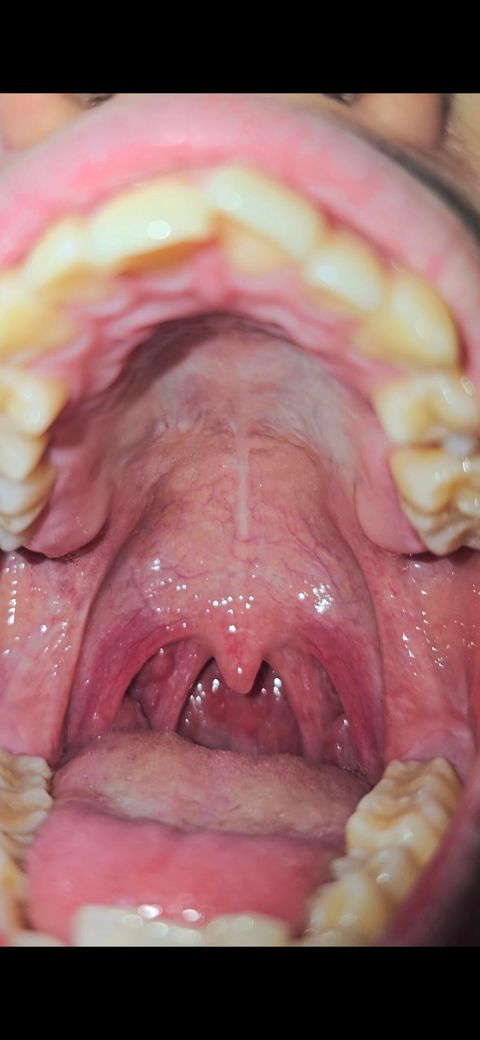

• 2번 째 사진

입천장 섬유화 인가요 과각화 인가요?

그리고 구강건조증 있어요. 입천장 봤을때 문제 있어보이나요? 하얀 판 같은 느낌도 들기도 하고 입천장이... 점막 소타액선에 문제 생겨서 침이 안나오는건 아니겠죠? ㅠㅠ

첨부하신 사진과 말씀만으로는 큰 이상소견 확인되는 바는 없어보입니다. 입천장에는 단단한 부분과 부드러운 부분 두 부분으로 나누어져 있으며 단단한 부분 있는 것이 정상 해부입니다. 특별히 사진에서는 과각화나 섬유화를 의심할만한 소견 보이지는 않습니다.

입천장은 일상생활 중의 다양한 자극에 의해 과각화 될 수 있습니다. 사진상으론 크게 이상이 있어보이진 않습니다